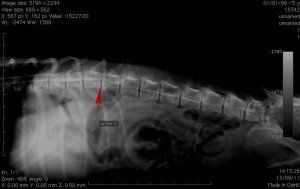

X-ray of the spine:

In case of locomotor difficulties, it is possible to identify vertebral lesions. on a radio without preparation. The injection of contrast product in the spine (myelography) is sometimes necessary to visualize possible compressions of the spinal cord (herniated discs) which can be responsible for paralysis in your animal.